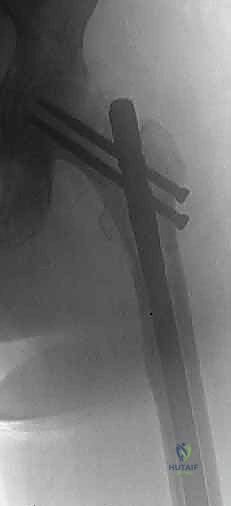

- اختيار نوع المفصل الاصطناعي: بناءً على صور الأشعة المقطعية، يحدد الجراح نوع المفصل. في حالات الأورام، غالباً ما تُستخدم مفاصل ذات جذوع طويلة (Long-stem prostheses) لتجاوز منطقة الورم وتثبيت المفصل في العظم السليم أسفل الآفة. كما تُستخدم تقنية الأسمنت العظمي (Bone Cement - PMMA) بكثافة لتوفير استقرار فوري للمفصل والسماح للمريض بالمشي في اليوم التالي.

الخطوة 4: تحضير عظم الفخذ وتثبيت الجذع (Femoral Stem Insertion)

- يتم تجويف القناة النخاعية داخل عظم الفخذ لتتناسب مع حجم الجذع المعدني (Stem).

- في مرضى السرطان النقيلي، يُفضل استخدام الأسمنت العظمي لتثبيت الجذع. الأسمنت العظمي لا يعمل كصمغ فقط، بل كحشوة تملأ الفراغات التي تركها الورم وتوفر دعماً ميكانيكياً فورياً.

- يتم وضع رأس معدني أو خزفي (Ceramic Head) على قمة الجذع.